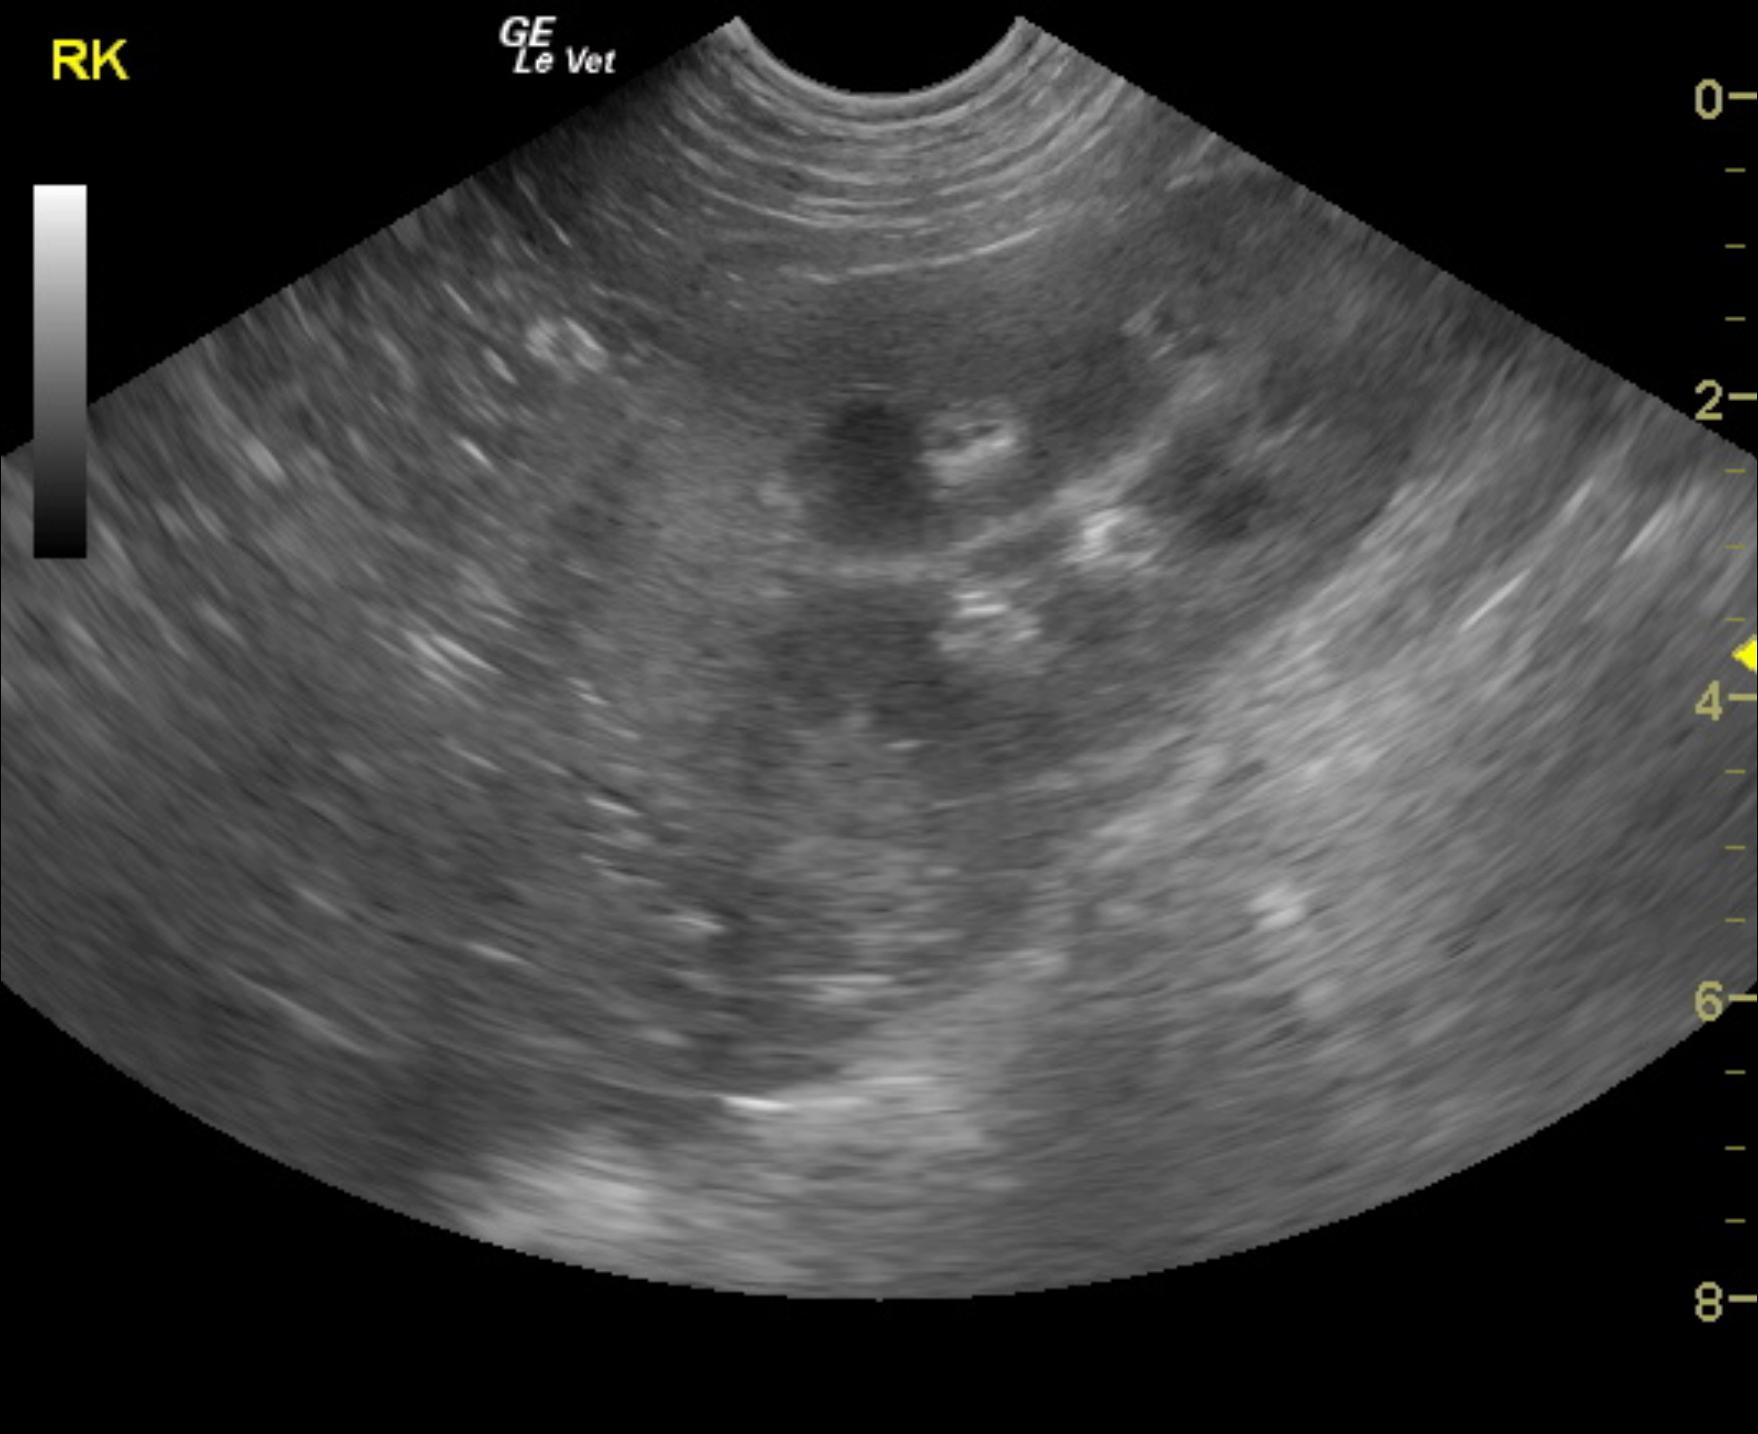

The patient is a canine English Bulldog, MN, 9 years, 67.5 lbs who was presented for vomiting and diarrhea. The patient is in renal failure. Urine specific gravity 1.017, 2+ protein, white count 11-20. Culture revealed E Coli. BUN 45, creatinine 3.6. Multiple, mild positives for Leptospirosis ( Leptospirosis titers positive. Pomona 1-200, Grippotyphosa 1-400. Autumnalis 1-200,

The patient is a canine English Bulldog, MN, 9 years, 67.5 lbs who was presented for vomiting and diarrhea. The patient is in renal failure. Urine specific gravity 1.017, 2+ protein, white count 11-20. Culture revealed E Coli. BUN 45, creatinine 3.6. Multiple, mild positives for Leptospirosis ( Leptospirosis titers positive. Pomona 1-200, Grippotyphosa 1-400. Autumnalis 1-200,